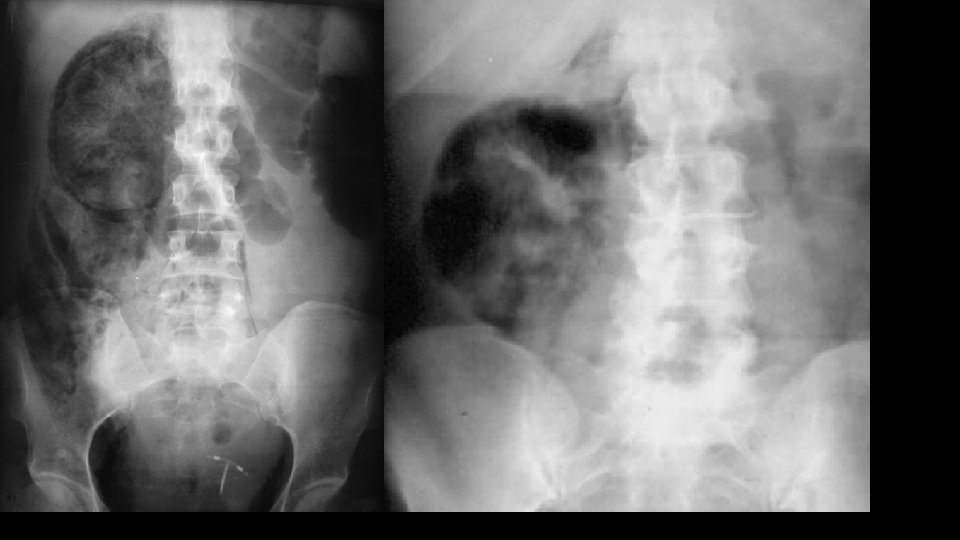

Urolithiasis Calculi along urinary tract • Anywhere • Kidney • Ureter • Bladder

C for calcifications • Calculi – here, there and everywhere • Organ calcifications

Mimics